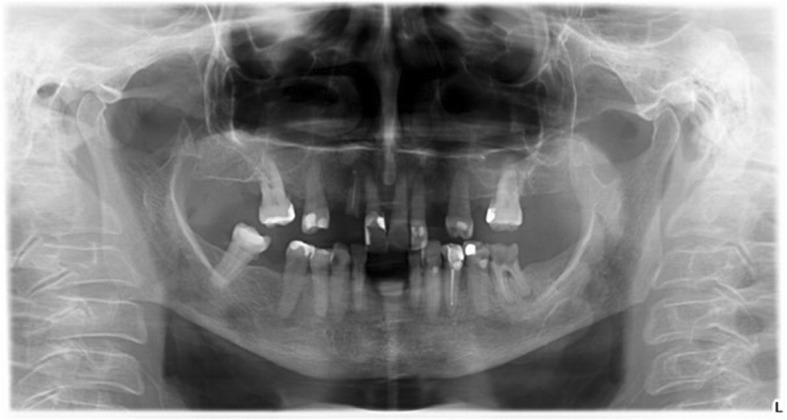

Moreover, a morphological classification of the mandibular cortical bone has been proceeded on panoramic radiographs. Mandibular cortical index (MCI) according to Klemetti et al. [20] was used to assess morphological changes in the inferior cortex of the mandible. Mandibular cortical shapes were analysed by observing the mandible distally from the mental foramina bilaterally and by categorizing them into one of the following three groups as previously described by Klemetti et al. [20]: “C1 – the endosteal margin of the cortex is even and sharp on both sides (Fig. 2); C2 - the endosteal margin shows semilunar defects (lacunar resorption) or endosteal cortical residues on one or both sides, mild to moderate cortex erosion (Fig. 3); C3 – the cortical layer forms heavy endosteal cortical residues and clearly porous, severely eroded cortex” (Fig. 4).

Fig. 4.

Panoramic radiograph with C3 category of MCI

The analysis of results obtained revealed 39 patients with osteopenia according to the phalanx T-score. The highest porosity inferior cortex (C3) was observed in 12 patients and in 10 of them phalanx T-score was < − 1. The mild eroded cortex (C2) was observed in 37 women and 13 of them showed osteopenia. Correlations between MCI and bones parameters indicated that in patients with a reduction of bone mass, the mandibular cortex shape was characterized by a higher porosity.

In women with C3 category of mandibular cortical index, phalanx Ad-SoS, phalanx T-score and the mandibular cortical width were significantly lower than in women with C2 and C1 category.